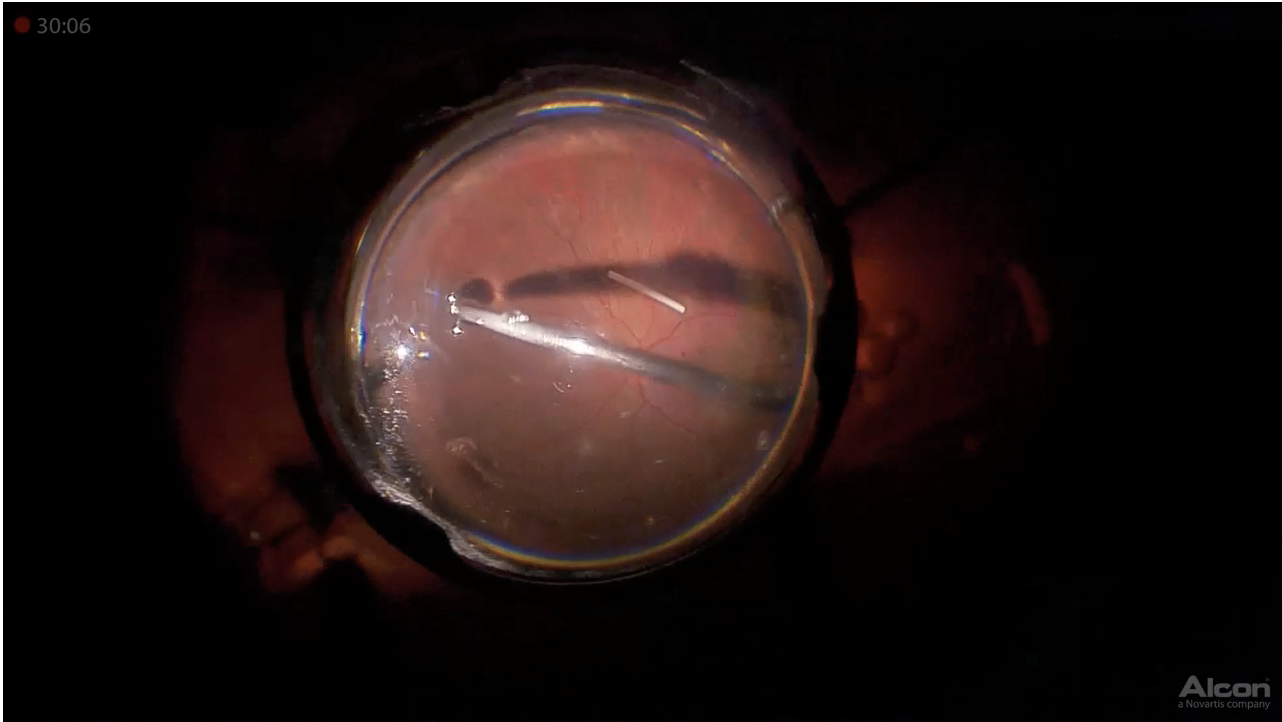

Dense Cataract

Anat Loewenstein, MD